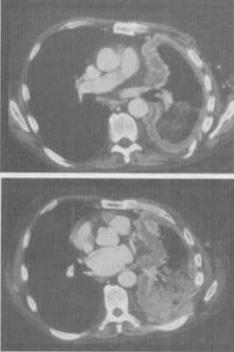

- 单项选择题 男,68岁,胸痛,呼吸困难,咳嗽1个月余,结合影像学检查,最可能的诊断是()。

- A